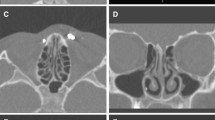

For the nasal conchae, uncinate process and the bony septae of the ethmoid cells, subjective image quality was comparable between the study and control group. For all other soft-tissue and bone-containing structures, image quality was different between both groups. For detailed results, see Table 3.

Bony structures (mastoid cells, nasal conchae etc.) were diagnostic with good image quality in both groups, soft tissues (optic nerve, retrobulbar fat etc.) were diagnostic with sufficient image quality in the study group because of a high level of noise.

Examples of typical cases are given in Figs. 2, 3, and 4.

Study group

Image quality of soft tissue structures (optic nerve, retrobulbar fat etc.) were sufficient (median score = 3). Mastoid and bony septae of the ethmoid cells, nasal conchae and uncinate process were rated excellent (median score = 5) and all other structures good (median score = 4). Contour delineation of the lamina cribrosa, the most delicate structure of this evaluation, was good.

Control group

Mastoid cells, bony septae of the ethmoid cells, nasal conchae, uncinate process and retrobulbar fat were rated excellent (median = 5). All other structures were rated good (median = 4). Contour delineation of the lamina cribrosa, the most delicate structure of this evaluation, was also rated good (median = 4).